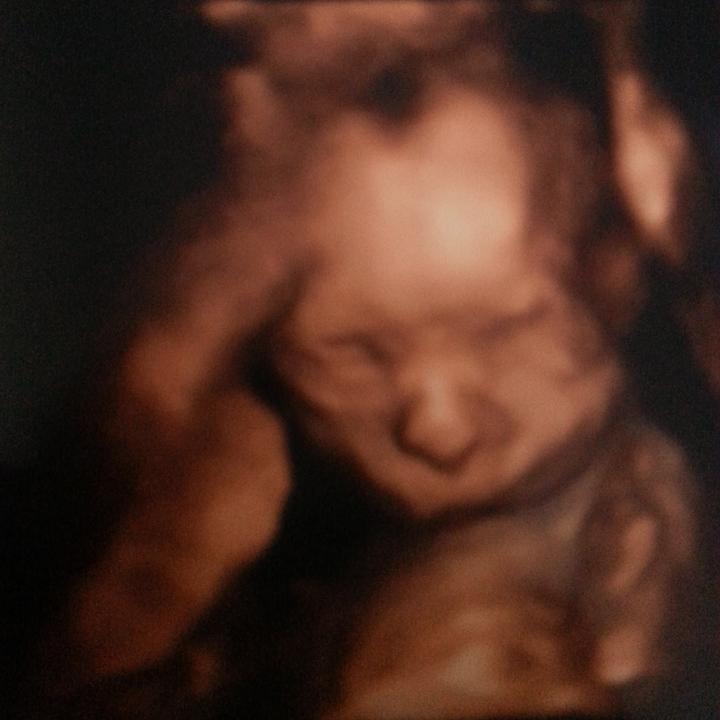

Pre našu malú princeznicku ♡

naša Laura :-*